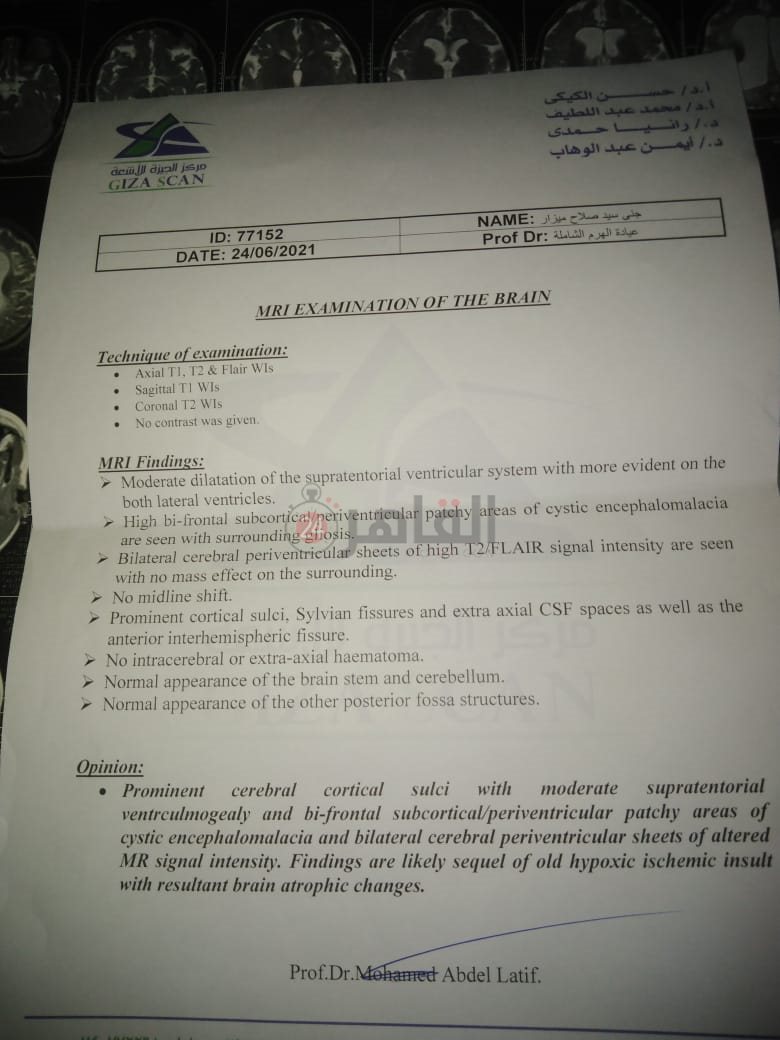

من جانبه، قال صلاح سيد، والد الطفلة جنى صلاح، إن ابنته تعاني من ضمور في المخ منذ ولادتها، نتيجة خطأ طبي، أدى إلى نقص كبير في الأكسجين لديها.

وأضاف في تصريحات خاصة لـ "القاهرة 24": "جنى تبلغ من العمر 6 سنوات، لا تستطيع المشي أو الوقوف على قدميها، نتيجة إصابتها بضمور في المخ منذ ولادتها".

وتابع: "مكنتش بتتحرك خالص، وجسمها طري، روحت كشفت عليها، وعملت أشعة وتحاليل كتير، أتأكدنا إصابتها بضمور في المخ"، مضيفًا:" مش بتعرف تأكل احنا اللي بنأكلها، هي عقلها كويس لكن مش بتتحرك ولا تتكلم".

وأوضح أن الطبيب الخاص بها أكد أن هناك داء خارج مصر يحسن من حالتها، ولكن باهظ الثمن، وتحتاج تناوله بشكل دوري.

واستكمل:" حاليًا تتناول أدوية شرب عادية، لحين توفيرالدولة علاجها من خارج مصر"، مشيرًا: "مفعتش قضية على الدكتور، ورضيت بقضاء ربنا".